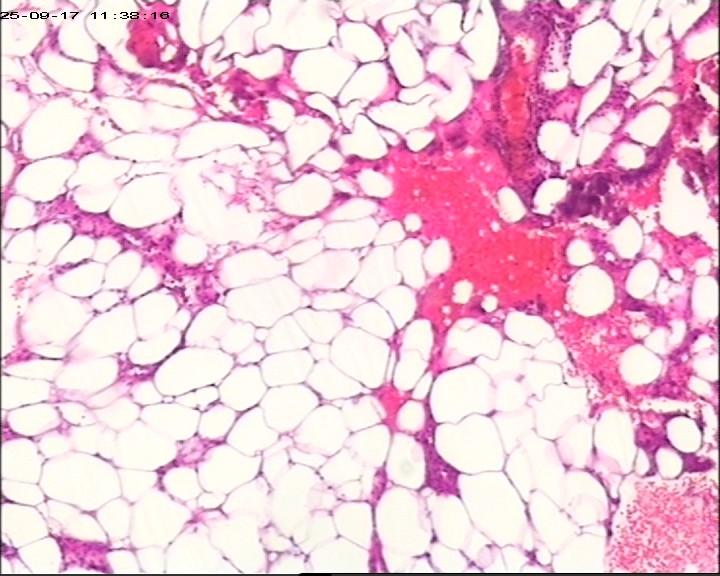

臀部组织,请帮忙看看,谢谢

性别

男

年龄

20岁

临床诊断

一般病史

藏毛窦或囊肿切开术

标本名称

臀部

大体所见

灰白灰黄碎组织一堆,大小为6.5*4*1cm。

描述诊断炎性病变